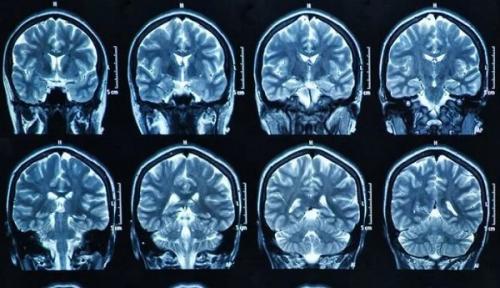

- Микроинсульт на МРТ. Инсульт на МРТ головного мозга

Клинические проявления исчезают в течение 24 часов, однако не бесследно для сосудов головного мозга. При микроинсультах возможен некроз очень малого участка головного мозга, который можно диагностировать лишь по результатам МРТ, компьютерной ангиографии. Данные виды диагностики доступны в Юсуповской больнице.

Микроинсульт на МРТ. Инсульт на МРТ головного мозга

Магнитно-резонансная томография представляет собой экстренный способ диагностики нарушения мозгового кровотока. Инсульт на МРТ головного мозга виден в первые же сутки после развития патологического процесса. Но для его выявления может потребоваться модификация метода, а не стандартная обзорная томография. МРТ после инсульта также проводится. Томография показывает степень нарушения кровотока, поражения тканей. Все же есть отдельные нюансы проведения магнитно-резонансной томографии при подозрениях на инсульт.

- Первый — стандартная обзорная томография. Долгие годы она была единственным вариантом диагностики патологического процесса. Благодаря нейровизуализации врачи получают возможность оценить состояние головного мозга, его отдельных участков. Области ишемии или геморрагии хорошо видны. Можно оценить степень нарушения, спрогнозировать вероятный исход, разработать метод грамотной терапии в определенном клиническом случае. У методики есть минус — она показывает состояние церебральных структур, выявляет патологический процесс только спустя как минимум сутки от развития расстройства. Для экстренного определения нарушения она не годится. Нужна более чувствительная методика.

- Второй — диффузионная МРТ. Эта модификация классического способа должна установить диагноз в первые 24 часа после наступления поражения церебральных структур. Томографический способ основан на способности МРТ-аппарата регистрировать особенности движения молекул воды в нервных тканях. Благодаря чему врачи получают возможность выявить область нарушения работы ЦНС, степень поражения в острейшем периоде.